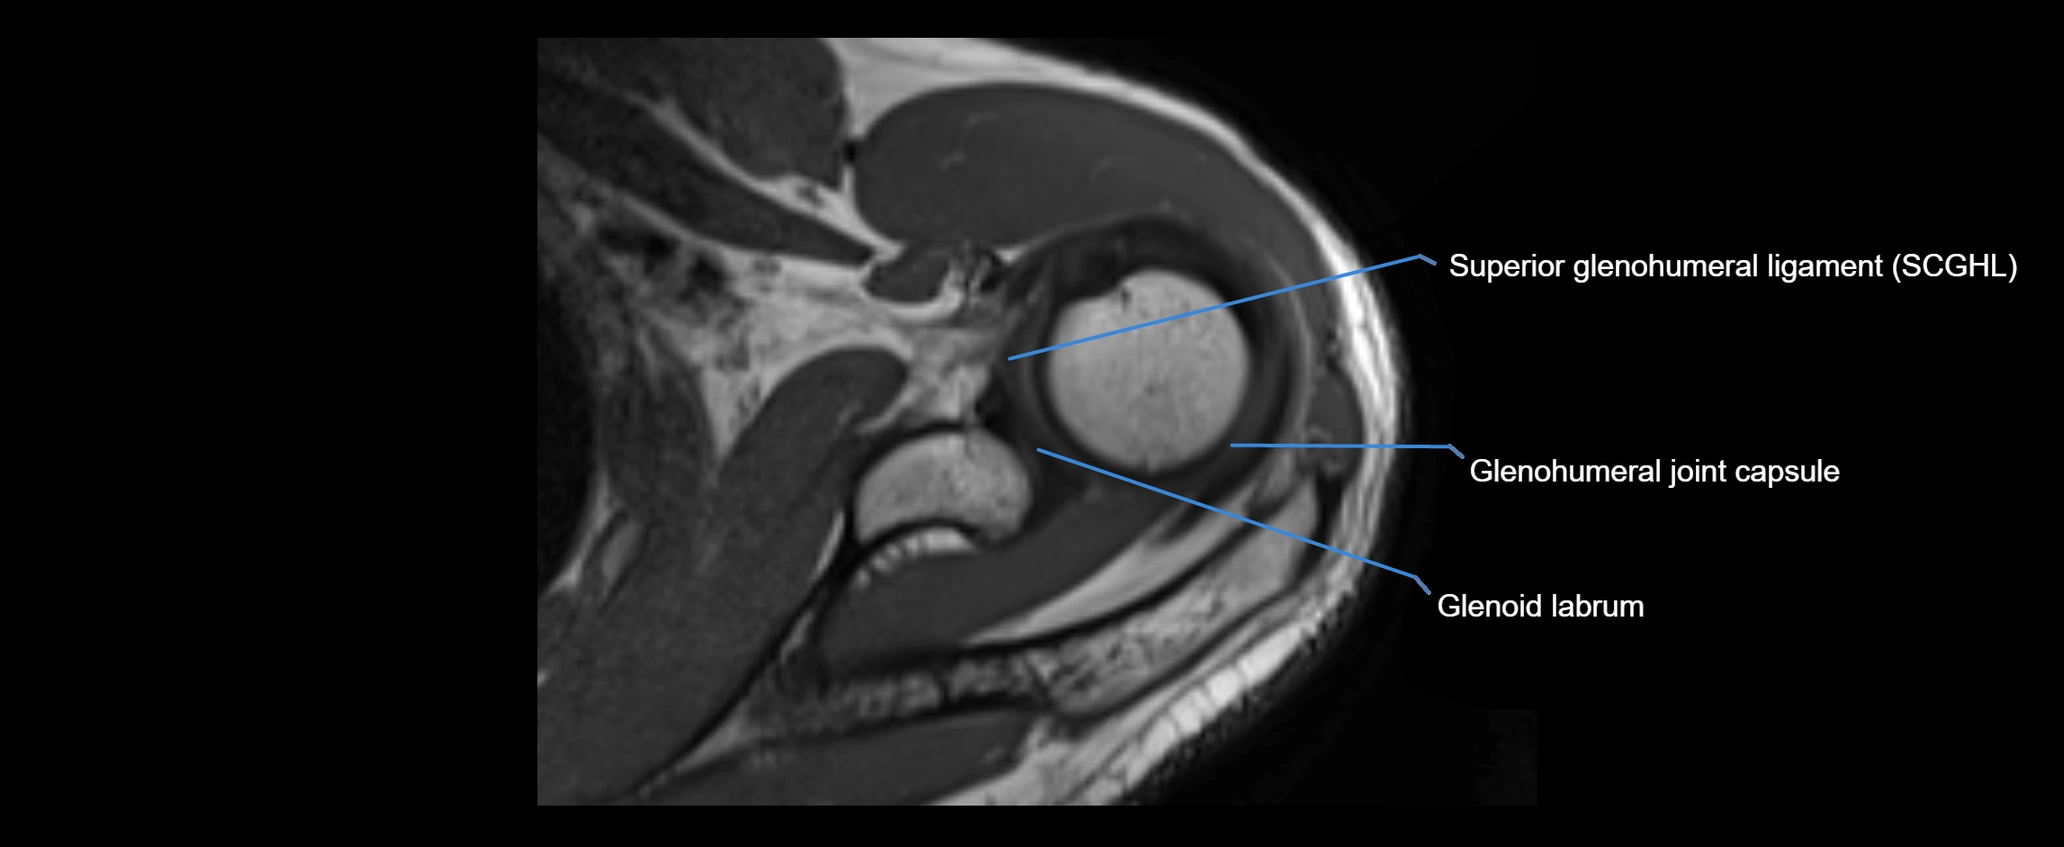

MRI images

image